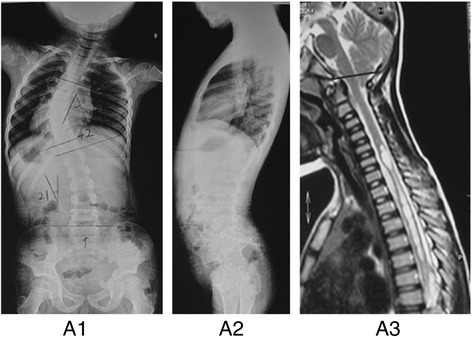

Fig. 1.

A 8-year-old boy diagnosed as presumed JIS with T5-T11 left-sided thoracic curve of 42° at first visit (A1-A2). He was screened by a full spinal MRI scan which demonstrated an Arnold-Chiari Type-I malformation combined with a moniliform syrinx extending from C5 –T5 seen on the T2 sagittal (A3). Then he underwent PFD (i.e. posterior fossa decompression)

94 (18.7 %) patients were found to have intraspinal neural axis abnormalities and all the positive findings of the spinal cord by MRI and their percentages were shown in Table 1. Totally Arnold-Chiari malformation with or without syringomyelia accounted for 64.8 % (61/94) of all these intraspinal neuro-axis abnormalities (Fig. 1) while diastematomyelia, tethered cord and intraspinal tumor were relatively uncommon. All the patients with neural axis abnormalities were referred to neurosurgical evaluation, treatment and follow-up accordingly.